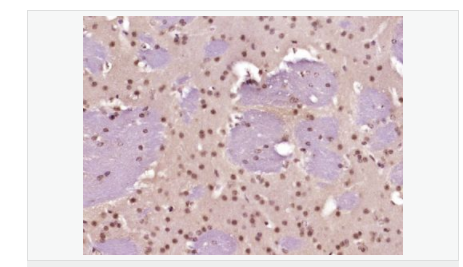

| 產品應用 | WB=1:500-2000 ELISA=1:5000-10000 IHC-P=1:100-500 IHC-F=1:100-500 Flow-Cyt=1ug/Test ICC=1:100-500 IF=1:100-500 (石蠟切片需做抗原修復) not yet tested in other applications. optimal dilutions/concentrations should be determined by the end user. |

| 細胞定位 | 細胞核 |